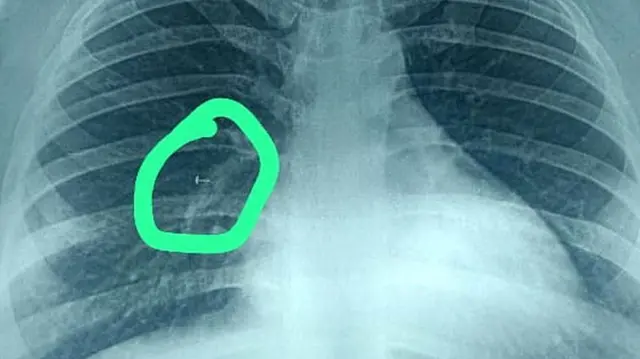

అయితే ఆమెకు మందులు పనిచేయకపోవడంతో ఊపిరితిత్తుల డాక్టర్ని సంప్రదించగా, ఆయన సీటీ స్కానింగ్ చేయించడంతో ఆమె ఊపిరితిత్తుల్లో చిక్కుకున్న వస్తువు కనిపించింది. ఎక్స్రేలో ఆ వస్తువు ఏమిటో తేలింది.

‘‘బ్రాంకోస్కోప్తో పదునైన వస్తువును బయటకు తీసుకురావడం చాలా కష్టమైన పనే. పైగా రెండు వారాలకు పైగా ఆ వస్తువు ఆమె ఊపిరితిత్తుల్లో ఉండిపోయింది. దాని చుట్టూ కణజాలం పెరగడం కూడా మొదలైంది. దానిని బయటకు తీసేటప్పుడు చాలా జాగ్రత్తగా ఉండాలి. ఇరుకైన వాయునాళాల్లోంచి దానిని బయటకు తీసుకువచ్చేటప్పుడు నాళాలు గాయపడి ప్రమాదంగా మారొచ్చు’’ అని జాష్ చెప్పారు.